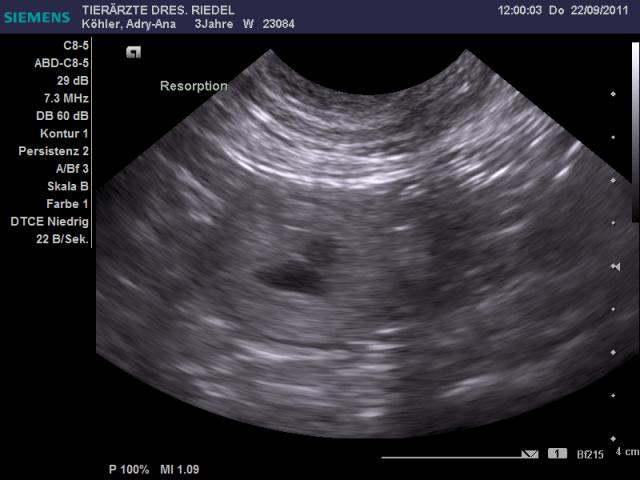

Adry-Ana-Fly wurde am 25./26.08.2011 vom Champion-Rüden Earl Grey Designed by Blue DeLux alias >>Robbi<< gedeckt. Die Verpaarung war erfolgreich und Adry-Ana-Fly hat am 25. 10. 2011 hübsche Welpenbabys auf die Welt gebracht. Fotos folgen in Kürze. Video von Adry & Robbi

Hier die ersten Bilder der Ultraschalluntersuchung: